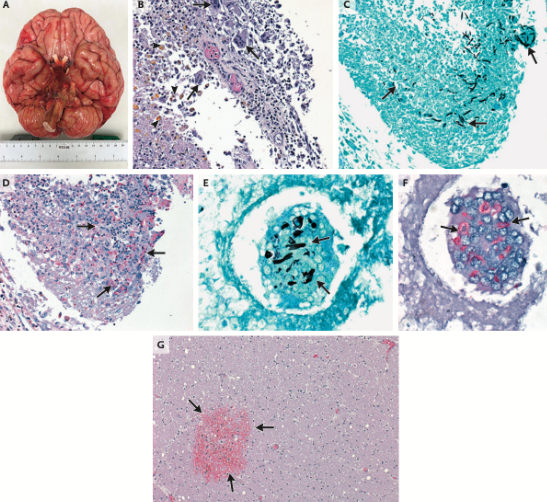

A multinational outbreak (185 exposed, 9 cases) of nosocomial Fusarium solani meningitis occurred among immunocompetent patients who underwent surgery with epidural anesthesia in Mexico in 2023 [12]. The pathogen showed high predilection for the brainstem and vertebrobasilar arterial system, with high mortality from vessel injury.

Rhinocerebral Mucormycosis:

- Most common form in diabetic patients

- Begins with sinusitis, facial pain

- Rapid progression with necrotic eschar (black eschar = late finding)

- Orbital involvement: Proptosis, vision loss

- Cavernous sinus thrombosis

- CNS extension: High mortality

Mucormycosis carries significant morbidity and mortality:

- Overall mortality: 40-80% depending on form and host

- Rhinocerebral with CNS extension: >80% mortality

- Disseminated disease: >90% mortality